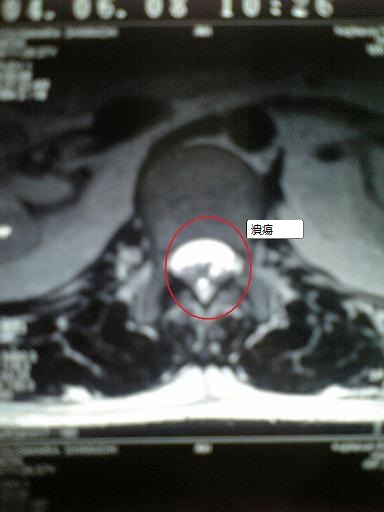

そこで胃カメラを飲んだら胃の中が糜爛状態になっていたのです。

火山がたくさん噴火しているような光景です。